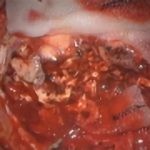

術中写真

摘出 前